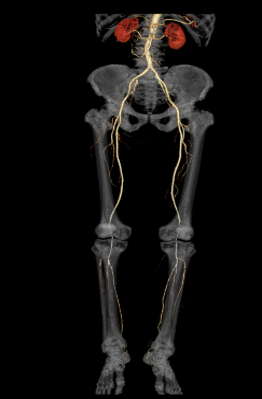

Large Bore for Wide Applications Positioning and scan flexibility for complex-type patient

76cm scan space/250kg table capacity and 21Lp/cm Resolution is easy to position obese patients comfortably without compromising dose and image quality